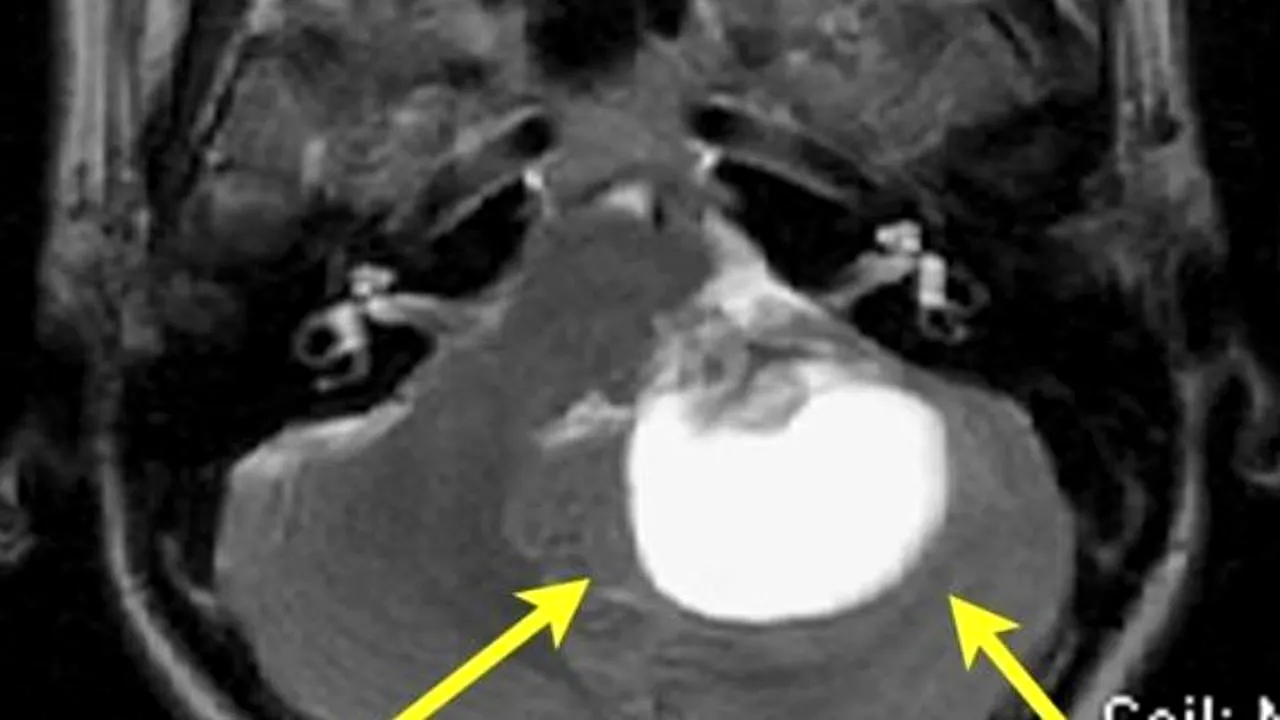

Americanca Stacey Kramer a fost diagnosticată, la vârsta de 43 de ani, cu o tumoare pe creier, de mărimea unei mingi de golf.

Americanca Stacey Kramer a fost diagnosticată, la vârsta de 43 de ani, cu o tumoare pe creier, de mărimea unei mingi de golf. După ce a învins boala, ea a relatat, în cadrul unui discurs motivațional susținut în fața unor tineri, că boala sa a fost precum „un cadou neprețuit” care a ajutat-o să își schimbe în bine viața.